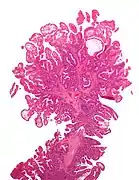

| Tubular adenoma | 2% at 1.5 cm[12] | Low to high grade dysplasia[13] | Over 75% of volume has tubular appearance.[14] | ![]() |

Adenomas

Neoplastic polyps of the bowel are often benign hence called adenomas. An adenoma is a tumor of glandular tissue, that has not (yet) gained the properties of cancer.

The common adenomas of the colon (colorectal adenoma) are the tubular, tubulovillous, villous, and sessile serrated (SSA).[18] A large majority (65–80%) are of the benign tubular type with 10–25% being tubulovillous, and villous being the most rare at 5–10%.[9]

Micrograph of a tubular adenoma, the most common type of dysplastic polyp in the colon